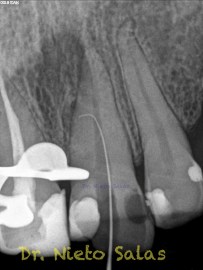

Y este sería el otro caso:

Es muy importante cambiar la proyección de las Rx para tener más información de como hemos sellado el sistema de conductos.

• Hola Juan, para empezar, muchas gracias por tu comentario.

Como sabrás, son muchas las piezas dentarias que presentan conductos laterales, lo primero, es descartar que la imagen pueda ser una fractura vertical, después conformo el sistema de conductos, y si sospecho de un conducto lateral ( INTUICIÓN ) precurvo una lima de pequeño diámetro y exploro las paredes en la zona de puede estar. En ocasiones, puedes ver un pequeño puntito, la entrada, con el microscopio. (es raro).